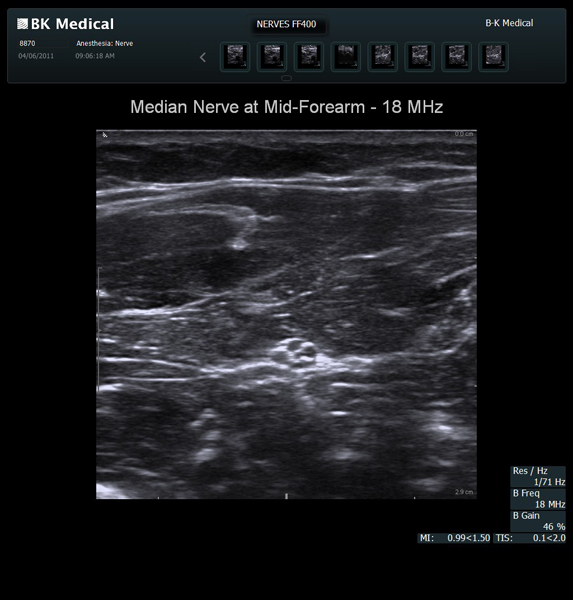

The Flex Focus 400 exp ultrasound system offers premium image quality with fast frame rates for excellent temporal resolution. The system features Automatic Mode Adjustment (AMA) to optimize high resolution B-Mode Imaging when changing modes and depth.

Transducers Designed for Guidance

BK Medical offers high-frequency linear transducers, imaging from 18-2 MHz for upper and lower extremities, and curved array abdominal transducer 8820e for special deep nerves or paravertebral/spinal applications. Our transducers provide superb detail that makes it easy to see your needle during procedures.